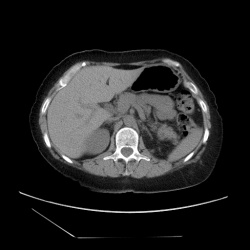

Женщина 40 лет. После колики слева. По УЗИ "камней нет".